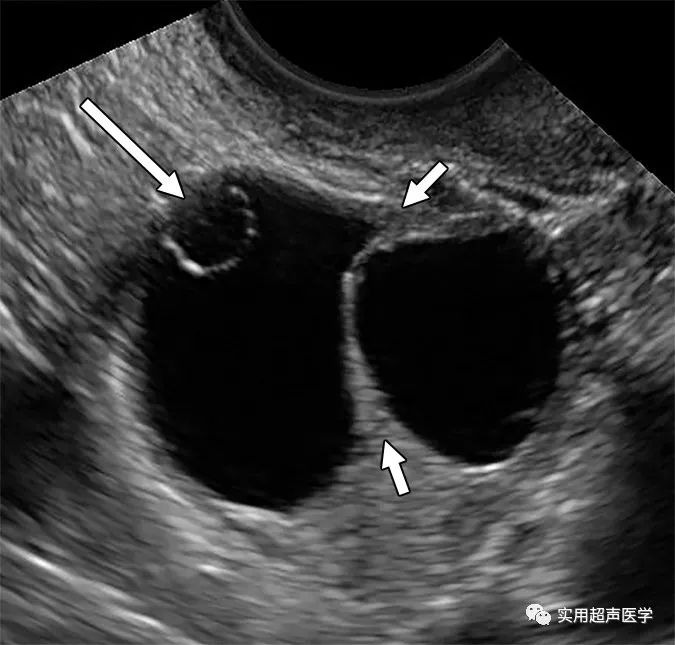

22岁女性,伴有继发性闭经。超声图像显示囊肿内囊肿外观或子囊肿(长箭头),代表相邻卵巢实质内单独卵泡的部分体积平均。发现不应与多房囊肿混淆。将两个相邻的卵泡或囊肿与单个纵隔囊肿区分开来也可能具有挑战性。可疑隔膜两侧的卵巢组织(小箭头)达到峰值(八字形征)可确认邻近卵泡并排除真正的纵隔囊肿。

另一个潜在的陷阱是将子囊肿误认为是多房囊肿。欣赏圆形和周围卵巢实质内的位置可排除纵隔病变。